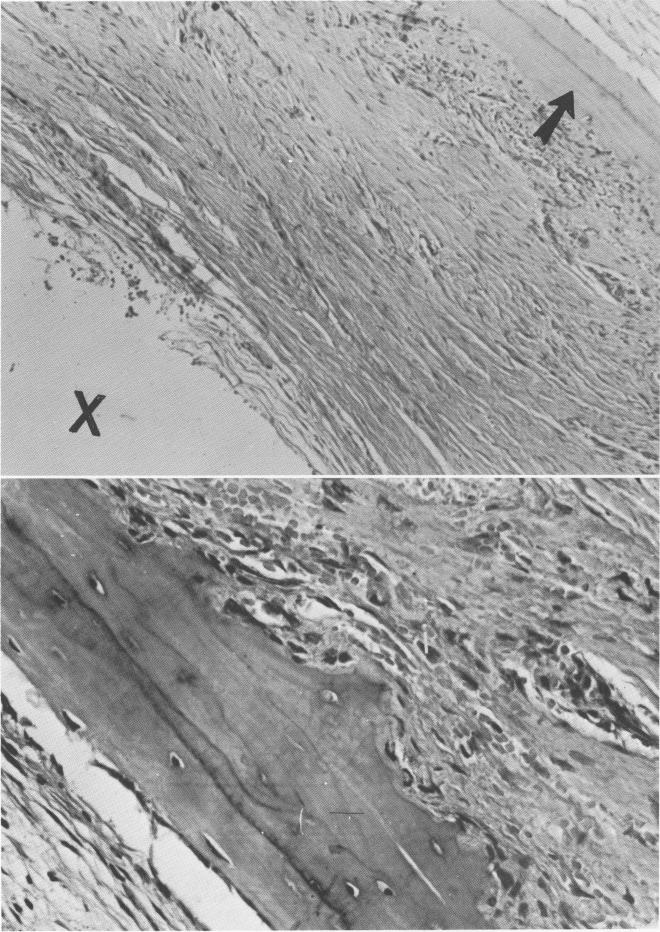

Histologic reports from Dr. George Greene, Jr., of the University of Buffalo, Buffalo, New York, revealed that the tissue adjacent to the bone-encapsulated implants was fibrous in nature, with the fiber content predominating and with a small amount of

cellularity (Fig. 4-42). Deeper in the tissue around each implant was a ring of bone. The side toward the implants exhibited active osteogenesis, indicating deposition of bone toward the implant site (Fig. 4-43). Other studies at this deeper level showed the inner aspect of the fibrous tissue as it butted against the implants (Fig. 4-44) . On the whole, fiber elements predominated over the cellular elements. However, near the implant there were more cells and the fiber

Fig. 4-43. A, In addition to the collagenous pseudoperiodontal membrane around the implant site (X), osteogenesis of the bone is seen (arrow) with the osteoblasts lined up toward the implant site. B, Under higher power, osteocytes are clearly visible in their lacunae.